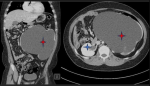

Diagnostic assessment: an abdominopelvic ultrasound scan revealed severe left hydronephrosis caused by uteropelvic junction (UPJ) obstruction. An abdominopelvic computer tomography (CT) scan, as shown in Figure 1, indicates severe left hydronephrosis, possibly due to uteropelvic junction obstruction. A full blood count and renal function test were done, and were seen to be normal.

Figure 1: abdominal CT scan showing grade 4 hydronephrosis of the left kidney; the red stars show hydronephrosis of the left kidney with no discernible renal parenchyma, and the blue stars show the normal right kidney